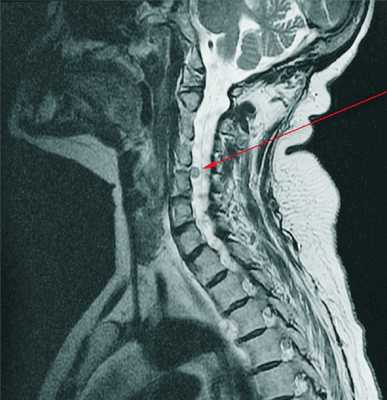

Считается, что основным моментом в возникновении остеохондроза является постоянная перегрузка позвоночно-двигательного сегмента, состоящего из двух соседних позвонков с расположенным между ними межпозвонковым диском. Такая перегрузка может возникать в результате двигательного стереотипа — осанка, индивидуальная манера сидеть и ходить. Нарушения осанки, сидение в неправильной позе, ходьба с неровным позвоночным столбом вызывают дополнительную нагрузку на диски, связки и мышцы позвоночника. Процесс может усугубляться из-за особенностей строения позвоночника и недостаточности трофики его тканей, обусловленных наследственными факторами. Чаще всего пороки в строении встречаются в шейном отделе (аномалия Кимерли, краниовертебральные аномалии, аномалия Киари) и приводят к сосудистым нарушениям и раннему появлению признаков остеохондроза шейного отдела позвоночника.

Разрушение соединительной ткани фиброзного кольца диска, связок и капсул фасеточных суставов вызывает реакцию иммунной системы и развитие асептического воспаления с отечностью фасеточных суставов и окружающих их тканей. Из-за смещения тел позвонков происходит растяжение капсул фасеточных суставов, а измененный межпозвонковый диск уже не так прочно фиксирует тела соседних позвонков. Формируется нестабильность позвоночного сегмента. Из-за нестабильности возможно ущемление корешка спинномозгового нерва с развитием корешкового синдрома. При остеохондрозе шейного отдела позвоночника это часто возникает во время поворотов головой, при остеохондрозе поясничного отдела — во время наклонов туловища. Возможно формирование функционального блока позвоночно-двигательного сегмента. Он обусловлен компенсаторным сокращением позвоночных мышц.

Все симптомы остеохондроза, проявляющиеся только в районе позвоночного столба, относятся к вертебральному синдрому. Все изменения, локализующиеся вне позвоночника, формируют экстравертебральный синдром. Это могут быть боли по ходу периферических нервов при сдавлении их корешков на выходе из спинного мозга. Например, люмбоишиалгия — боли по ходу седалищного нерва при остеохондрозе поясничного отдела позвоночника. При остеохондрозе шейного отдела позвоночника это сосудистые нарушения в вертебро-базилярном бассейне головного мозга, вызванные сдавлением позвоночной артерии.

Диагностику остеохондроза позвоночника проводит невролог или вертебролог. На начальном этапе производят рентгенографию позвоночника в 2-х проекциях. При необходимости могут сделать съемку отдельного позвоночного сегмента и съемку в дополнительных проекциях. Для диагностики межпозвонковой грыжи, оценки состояния спинного мозга и выявления осложнений остеохондроза применяют магнитно - резонансную томографию (МРТ позвоночника). Большую роль играет МРТ в дифференциальной диагностике остеохондроза и других заболеваний позвоночника: туберкулезный спондилит, остеомиелит, опухоли, болезнь Бехтерева, ревматизм, инфекционные поражения. Иногда в случаях осложненного остеохондроза шейного отдела позвоночника необходимо исключение сирингомиелии. В некоторых случаях при невозможности проведения МРТ показана миелография.